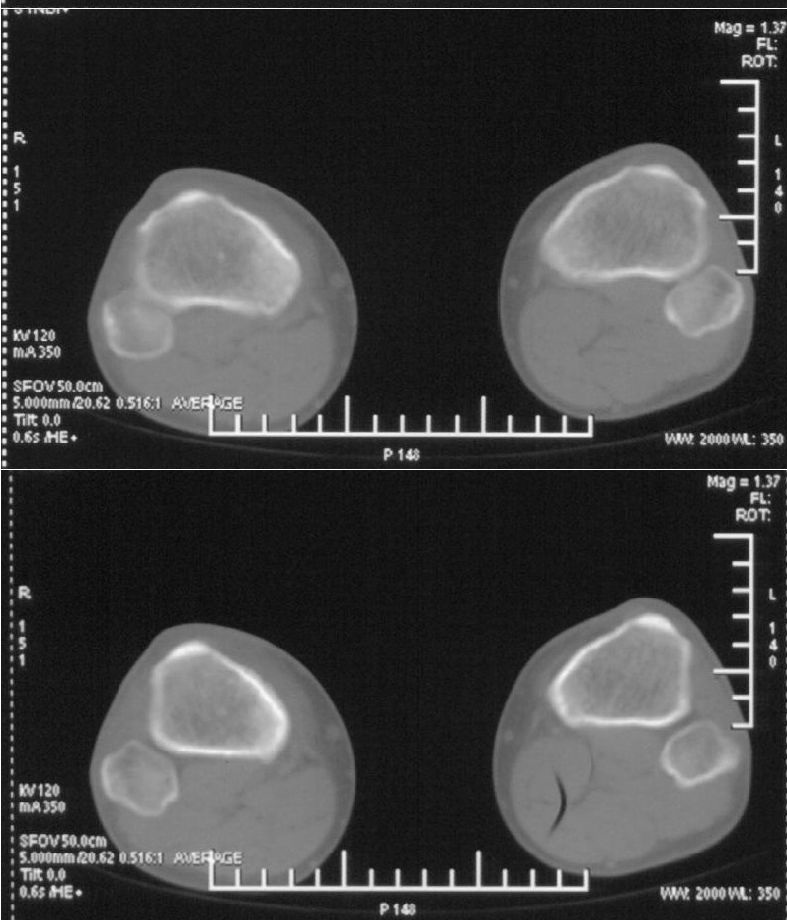

男,42岁。4个月前钢筋钝伤右侧小腿部,当时因无明显外伤,未引起重视。一周后因受伤腿部疼痛,发现肿胀,随后到当地医院进行检查(2008年4月16日)。因未发现骨质异常未引起重视,仅仅进行口服抗生素治疗处理。经过一段时间治疗但未见明显治疗效果在5月29日又进行x线检查,发现有胫骨密度上段密度增高,又进行抗炎治疗,仍未见效果。又在7月3日进行x线检查,仍然报告有胫骨上端密度增高,并建议ct检查。以下是相关检查结果:

髓腔密度呈絮状增高,胫骨上端内侧可见层状骨膜反应,考虑骨髓炎.

髓腔密度呈絮状增高,胫骨上端内侧可见层状骨膜反应,肌间隙模糊,考虑骨髓炎.

破坏、增生、骨膜反应,考虑骨髓炎